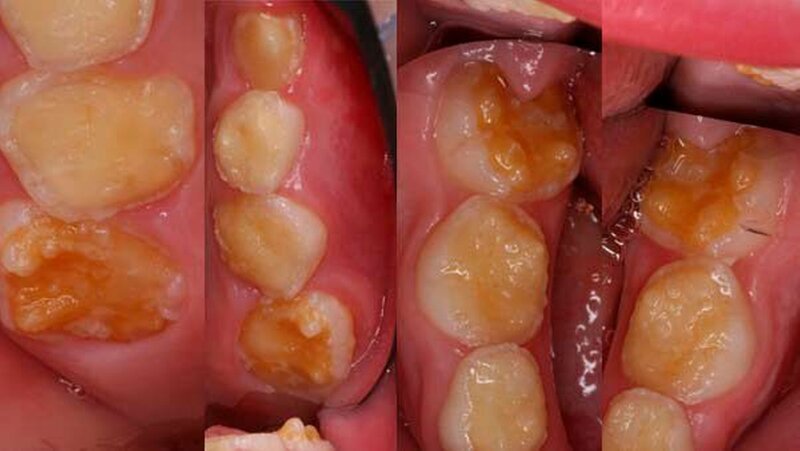

Der klinische Befund zeigte an beiden Dentitionen eine rauhe, zum Teil verminderte, bis fehlende Schmelzdicke und eine teilweise bräunliche Zahnverfärbung. Letztere wurden auch durch exogene Pigmenteinlagerung verursacht (Abbildung 1b und Abbildung 2).

Im radiologischen Befund konnte teilweise ein Kontrast zwischen Schmelz und Dentin festgestellt werden, jedoch war bei beiden Dentitionen eine verminderte Schmelzdicke ersichtlich (Abbildung 4). Auf Grund der radiologischen und klinischen Beurteilung konnte die Diagnose Amelogenesis imperfecta generalisata vom hypoplastischen Typ gestellt werden.